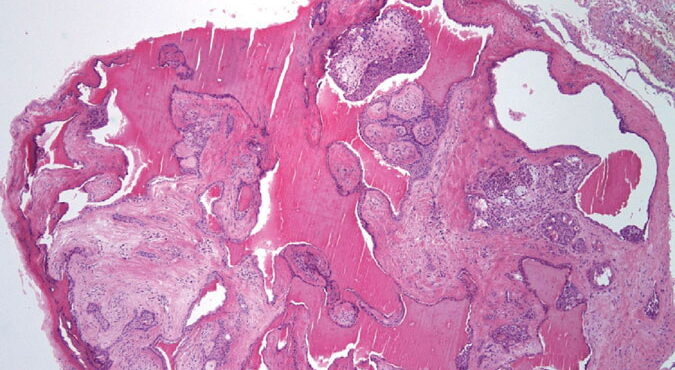

Herpes simplex = العقبول البسيط

Herpes simplex = العقبول البسيط OLYMPUS DIGITAL CAMERA OLYMPUS DIGITAL CAMERA OLYMPUS DIGITAL CAMERA OLYMPUS DIGITAL CAMERA OLYMPUS DIGITAL CAMERA OLYMPUS DIGITAL CAMERA OLYMPUS DIGITAL CAMERA OLYMPUS DIGITAL CAMERA OLYMPUS DIGITAL CAMERA